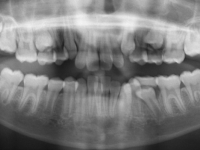

El paciente M.C. acude a nuestra consulta por:

– Apiñamiento importante

– Perfil convexo

– Forma arcada estrecha

-sobremordida

Con lo que decide realizarse un tratamiento de ortodoncia de duración de 26 meses con brackets smartclip 022 de acero.

Fotos antes tratamiento:

Plan tratamiento:

– Decidimos extraer 14.24.34.44

– Colocamos microtornillo lado izquierdo

– Gomas en triángulo para conseguir oclusión perfecta.